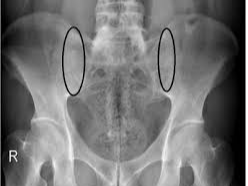

강직성 척추염은 주로 척추와 천장관절(골반 부위의 관절)에 만성 염증이 발생하는 자가면역성 질환입니다. 시간이 지남에 따라 염증이 반복되면서 척추뼈가 서로 융합되는 현상이 일어날 수 있어, 척추가 굳고 유연성을 잃게 됩니다. 이로 인해 자세가 변형되고 통증이 심해지는 특징을 보입니다. 비교적 젊은 나이에 발병하는 경우가 많으며, 남성에게서 더 흔히 나타나는 경향이 있습니다.

- 영상 검사: 엑스레이나 MRI를 통해 척추와 천장관절의 염증 및 손상을 확인합니다.